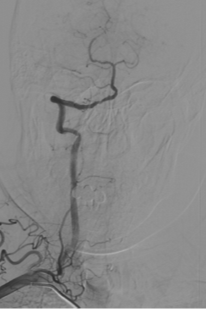

辅助检查(DSA)

主动脉弓+L-CA

波科支架怎么样径技-弓上病例大赏|第210期·右侧颈内动脉球囊扩张术+支架植入术_https://www.jmylbn.com_新闻资讯_第11张

R-CA

波科支架怎么样径技-弓上病例大赏|第210期·右侧颈内动脉球囊扩张术+支架植入术_https://www.jmylbn.com_新闻资讯_第12张